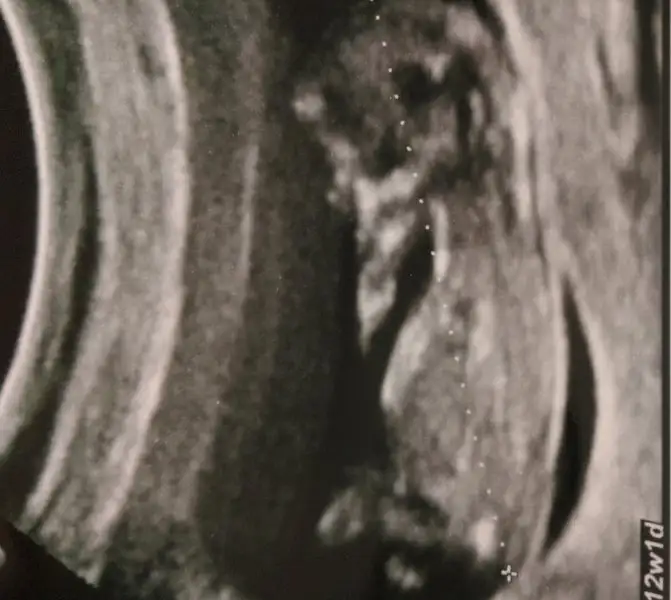

yani sağdan bakıyorum kız görüyorum,soldan bakıyorum erkek diyorum ahahahahaa ,.. hiçbirşey görmüyorum açıkçası ve hissetmiyorum,daha da enteresan olan içimde ağır basan bir cinsiyette yok.dün doktora sorsam muhtemelen aşşağı yukarı bir tahminde bulunurdu çünkü mübarek çocugun yeni oluşmaya başlayan mesanesini bile gördü,kesin cinsiyetini de görmüştür aama dilimin ucuna geldi geldi soramadım,öğrenmek istemedim çok ilginçÇok tatlısındemek var fikrin içimde mi kalsın diyorsun

ben kadına hiçbirşey sormadım. o baktı baktı hemşireye söylüyor bir yandan yazması için.ben de terimlere aşinayım anlıyorum zaten diye hiçbirşey sormadım,biz böyle bir yandan da tatlı tatlı genel sohbet ediyoruz kadınla siyasetten süriyeli mültecilerden sağlık sektöründen falan konuşuyoruz. dedim bukadar tatlı tatlı konuşuyor belki cinsiyetide laf arasında söyleyiverir hazır samimi bir ortam var ama ı-ıhhh yok söylemedi valla.sofiarya benimde kontrolum vardı.bende orasi iyimi burası normalmi diye sorup sorup üstüne cinsiyeti goruluyormu diyemendim.utandım. valla.:)kendimde hicbisey hiseetmiyorum aynı sen gibi.basklarina duydugum anda tahmin yapabiliyorum ama kendime hayrim yok:)bu arada ense kalınlığı 1.1dedi sormasam soylemicekti herhalde.bu doktorlari anlamak zor.yada işlerine karislliyormus gibimi hissediyorlar acaba.yukleyebilirsem bende bi ultrason foto koycam.tahminlere acigim teyzeler:)

Ya bakti ama soylemedi emin olamadi bakalim hayirlisi olsun. Saglikli sihhatli olsunda kizlsr gerisi onemli degil.canim nubu gorunmuyor bence erkek dik oldugu icin bacak arasindan cikmiypr yan bakinc.ama cene yapisi sivri bu cogu zaman kizıarda oluyor.ama cikintiya pek takiıma.bizim11+2de paraleldi am 12+4de net olrak erkek cinsiyyet gorduk.bqcak arasina bakmadi mi doktor?